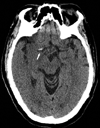

Background and purpose: The purpose of this study was to provide the first correlative study of the hyperdense middle cerebral artery sign (HMCAS) and gradient-echo MRI blooming artifact (BA) with pathology of retrieved thrombi in acute ischemic stroke.

Methods: Noncontrast CT and gradient-echo MRI studies before mechanical thrombectomy in 50 consecutive cases of acute middle cerebral artery ischemic stroke were reviewed blinded to clinical and pathology data. Occlusions retrieved by thrombectomy underwent histopathologic analysis, including automated quantitative and qualitative rating of proportion composed of red blood cells (RBCs), white blood cells, and fibrin on microscopy of sectioned thrombi.

Results: Among 50 patients, mean age was 66 years and 48% were female. Mean (SD) proportion was 61% (±21) fibrin, 34% (±21) RBCs, and 4% (±2) white blood cells. Of retrieved clots, 22 (44%) were fibrin-dominant, 13 (26%) RBC-dominant, and 15 (30%) mixed. HMCAS was identified in 10 of 20 middle cerebral artery stroke cases with CT with mean Hounsfield Unit density of 61 (±8 SD). BA occurred in 17 of 32 with gradient-echo MRI. HMCAS was more commonly seen with RBC-dominant and mixed than fibrin-dominant clots (100% versus 67% versus 20%, P=0.016). Mean percent RBC composition was higher in clots associated with HMCAS (47% versus 22%, P=0.016). BA was more common in RBC-dominant and mixed clots compared with fibrin-dominant clots (100% versus 63% versus 25%, P=0.002). Mean percent RBC was greater with BA (42% versus 23%, P=0.011).

Conclusions: CT HMCAS and gradient-echo MRI BA reflect pathology of occlusive thrombus. RBC content determines appearance of HMCAS and BA, whereas absence of HMCAS or BA may indicate fibrin-predominant occlusive thrombi.